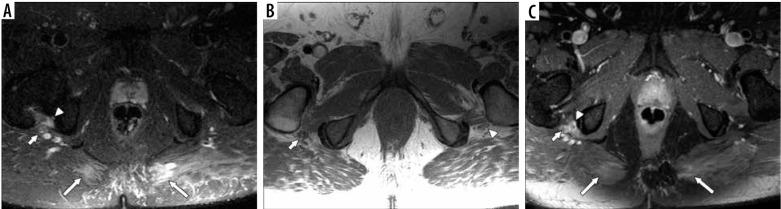

In this case series, we describe the magnetic resonance neurography (MRN) findings in 3 critically ill patients who presented with new onset of peripheral neuropathies in the extremities, and we discuss possible common mechanisms of nerve injury, including the role of position-related nerve injury.

MRN can be useful in identifying and localizing peripheral nerve abnormalities in the extremities of COVID-19 patients, and patients who are placed in the prone position during ventilation may be more susceptible to these injuries.